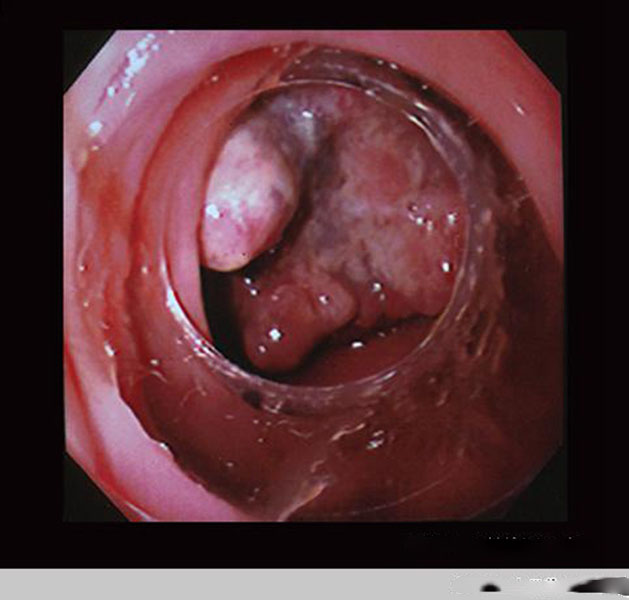

直腸腫瘤惡性腸鏡